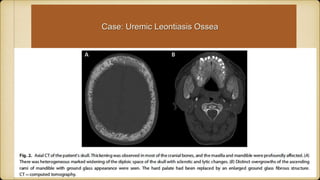

• #6 The scout film demonstrates overgrowth of the jaw, in particular the maxilla, with classical salt and pepper sign (arrow); found as multiple tiny well-defined calvarial lucencies in background of sclerotic ground-glass appearance associated with indistinct inner and outer tables